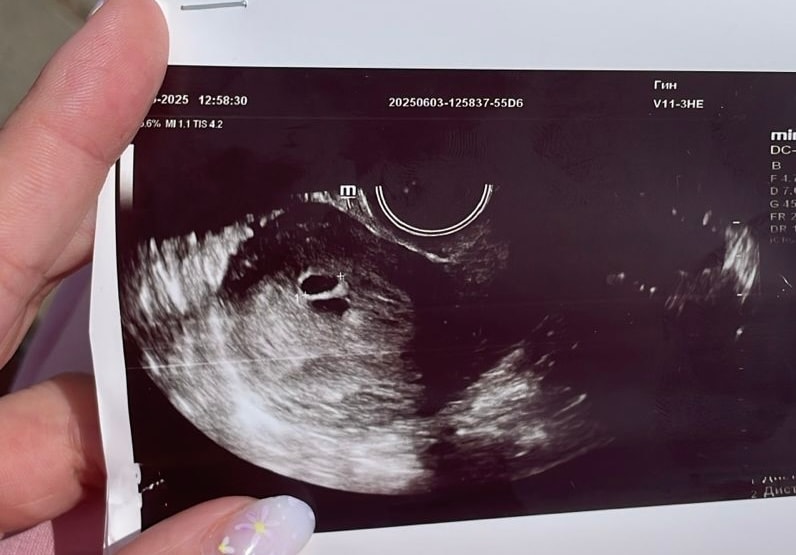

Лариса , как только датчик засунула,врач сразу сказала,а вы знаете что у вас 2 пя,я говорю нет. Потом стала сомневаться,я спросила а это может быть гематома,она сказала,что 100% не гематома,так как внутри нет жидкости,то есть крови. Я говорю,а почему один очерченный,а другой нет. Она сказал,что возможно один может просто отставать в развитии. И назначила контрольное узи через неделю

Евгения, в двух местах была на узи сегодня,нигде не сказали про гематому

Kristina, похоже на то😂 вчера девочки писали что это гематома,а сегодня в больнице,сказали что второе пя,но срок маленьки эмбриончиклв еще не видно